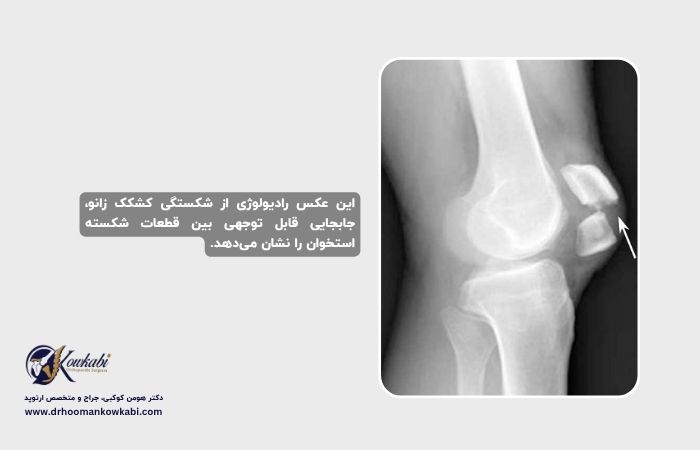

رادیوگرافی

رادیوگرافی تصاویری از ساختارهای متراکم مانند استخوان ارائه میدهد. جراح ارتوپد از زوایای مختلف رادیوگرافی تجویز میکند تا به دنبال شکستگی بگردد و تراز استخوانها را مشاهده کند. اگرچه نادر است، اما ممکن است فردی با استخوانهای اضافی در کشکک زانو متولد شود که با هم رشد نکردهاند. این وضعیت به نام پاتلای دو بخشی شناخته میشود و میتواند با شکستگی اشتباه گرفته شود. رادیوگرافی به شناسایی پاتلای دو بخشی کمک میکند. از آنجا که بسیاری از افراد این وضعیت را در هر دو زانو دارند، جراح ارتوپد ممکن است از زانوی دیگر شما نیز رادیوگرافی بگیرد.